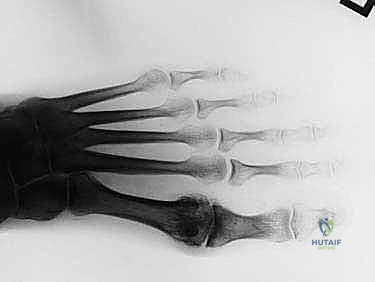

- التصوير بالأشعة السينية (X-rays): يتم أخذ صور بأوضاع تحمل الوزن (Weight-bearing). هذا الإجراء أساسي لتحديد مرحلة المرض، وتقييم حجم النتوءات العظمية، وقياس المسافة المفصلية المتبقية.

أيها المرضى الكرام، مرحباً بكم في هذا الدليل الطبي الموسع والشامل الذي نضعه بين أيديكم ليكون المرجع الأول باللغة العربية حول حالة "إبهام القدم المتصلب". تُعد هذه الحالة واحدة من أكثر مشاكل القدم شيوعاً وإيلاماً، وهي عبارة عن شكل من أشكال التهاب المفاصل التنكسي (الفصال العظمي) الذي يضرب المفصل المشطي السلامي الأول (1st MTP Joint) – وهو المفصل الحيوي الذي يربط إبهام قدمك ببقية القدم.

يعمل هذا المفصل كنقطة ارتكاز أساسية في كل خطوة تخطوها. عندما تمشي أو تركض، يحمل هذا المفصل وزناً يعادل ضعف وزن جسمك تقريباً. في حالة إبهام القدم المتصلب، يتآكل الغضروف الأملس الذي يغطي نهايات العظام، مما يؤدي إلى احتكاك العظم بالعظم. واستجابة لهذا الاحتكاك، يقوم الجسم بتكوين زوائد أو نتوءات عظمية (Osteophytes) حول المفصل، خاصة في الجزء العلوي (الظهري) منه. هذه النتوءات تعمل كمصدات ميكانيكية تمنع الإبهام من الانثناء لأعلى (الانثناء الظهري)، وهو ما يجعل عملية دفع القدم عن الأرض أثناء المشي أمراً بالغ الصعوبة والألم.

- رأس المشط الأول (First Metatarsal Head): هو السطح المفصلي المحدب الذي يشكل الجزء الأكبر من المفصل. في حالة إبهام القدم المتصلب، نلاحظ بشكل مميز تآكل الغضروف في النصف العلوي من هذا الرأس، وتكون نتوءات عظمية ضخمة على جانبه الظهري (العلوي). هذه النتوءات هي الجاني الرئيسي وراء الألم ومحدودية الحركة.

- قاعدة السلامية القريبة (Proximal Phalanx Base): هو السطح المفصلي المقعر الذي يتمفصل مع رأس المشط. يمكن أن تتكون نتوءات عظمية ظهرية أو عظام صغيرة (Ossicles) هنا أيضاً، مما يساهم في الانحشار (Impingement) عند محاولة ثني الإصبع لأعلى.